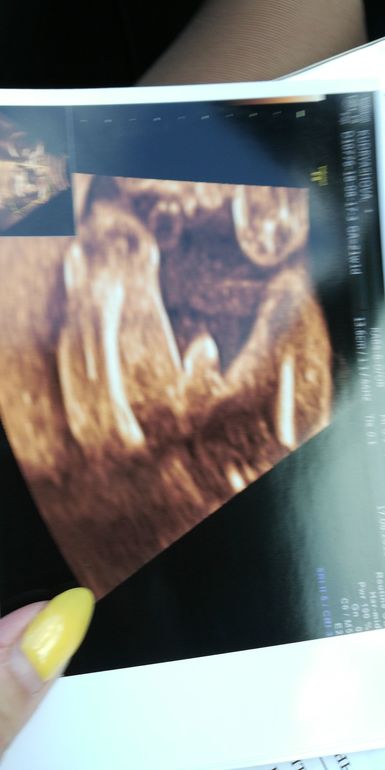

узи 16 авг-девочка

А мне кажется и на первом фото девочка)) у мальчиков "это" острее, чётче что ли

Я не выдержала.Пошла сегодня на определение пола-девочка без сомнений.Мне кажется у меня муж не так расстроился как я.Хотя я вначале очень боялась мальчика и не знала,что с ним делать.Долгожданный и запланированный ребенок,мы с мужем говорили о том,что без разницы какой пол,что просто хотим еще малыша.А на деле вон какие эмоции прут,а я ничего с собой не могу поделать.Еще даже не разобралась,нужно время,чтоб принять.Одно поняла я точно-раньше 20 недель нечего спрашивать пол ребенка. А на вашем фото все-таки мальчик-стручок длинненький,а у нас,видимо,были припухшие половые губки.Хотя сегодня в том же центре и на том же экране совсем не та точность изображения